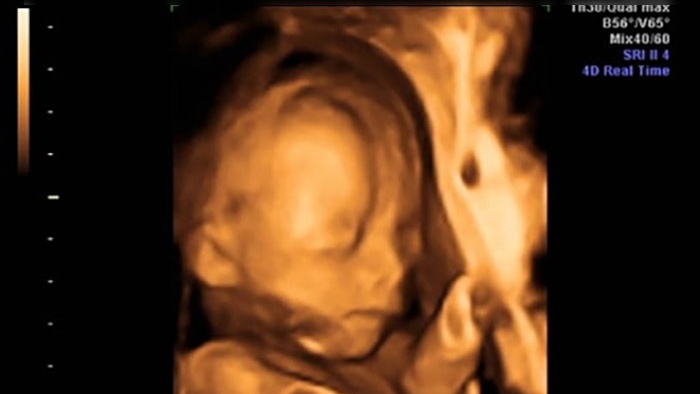

Siêu âm 4D, còn được gọi là siêu âm 4 chiều, là kỹ thuật chẩn đoán hình ảnh hiện đại, cho phép quan sát trực tiếp hình ảnh và hoạt động của thai nhi trong bụng mẹ tại thời điểm thực hiện. Kỹ thuật này sử dụng đầu dò truyền sóng âm, di chuyển trên da bụng của sản phụ để hiển thị hình ảnh và cử động của thai nhi dưới dạng video trực tiếp trên màn hình.

Nhờ siêu âm 4D, cha mẹ có thể thấy rõ các cử động và biểu cảm của thai nhi như cười, mếu, mút tay, nhăn mặt,... Ngoài ra, các chỉ số về sinh trắc và cấu trúc cơ thể thai nhi cũng được hiển thị, giúp bác sĩ phân biệt giữa hình ảnh bình thường và bất thường, từ đó đưa ra phương pháp xử trí phù hợp.

Trong quá trình siêu âm, bác sĩ sẽ sử dụng đầu dò truyền sóng âm di chuyển trên da bụng của sản phụ để ghi lại hình ảnh và cử động của thai nhi. Nếu phát hiện có dấu hiệu sứt môi, hình ảnh sẽ cho thấy rõ ràng các đặc điểm bất thường trên khuôn mặt của thai nhi. Phát hiện sớm qua siêu âm 4D giúp các bác sĩ và gia đình có thể chuẩn bị tốt hơn cho việc chăm sóc và điều trị sau khi bé chào đời.